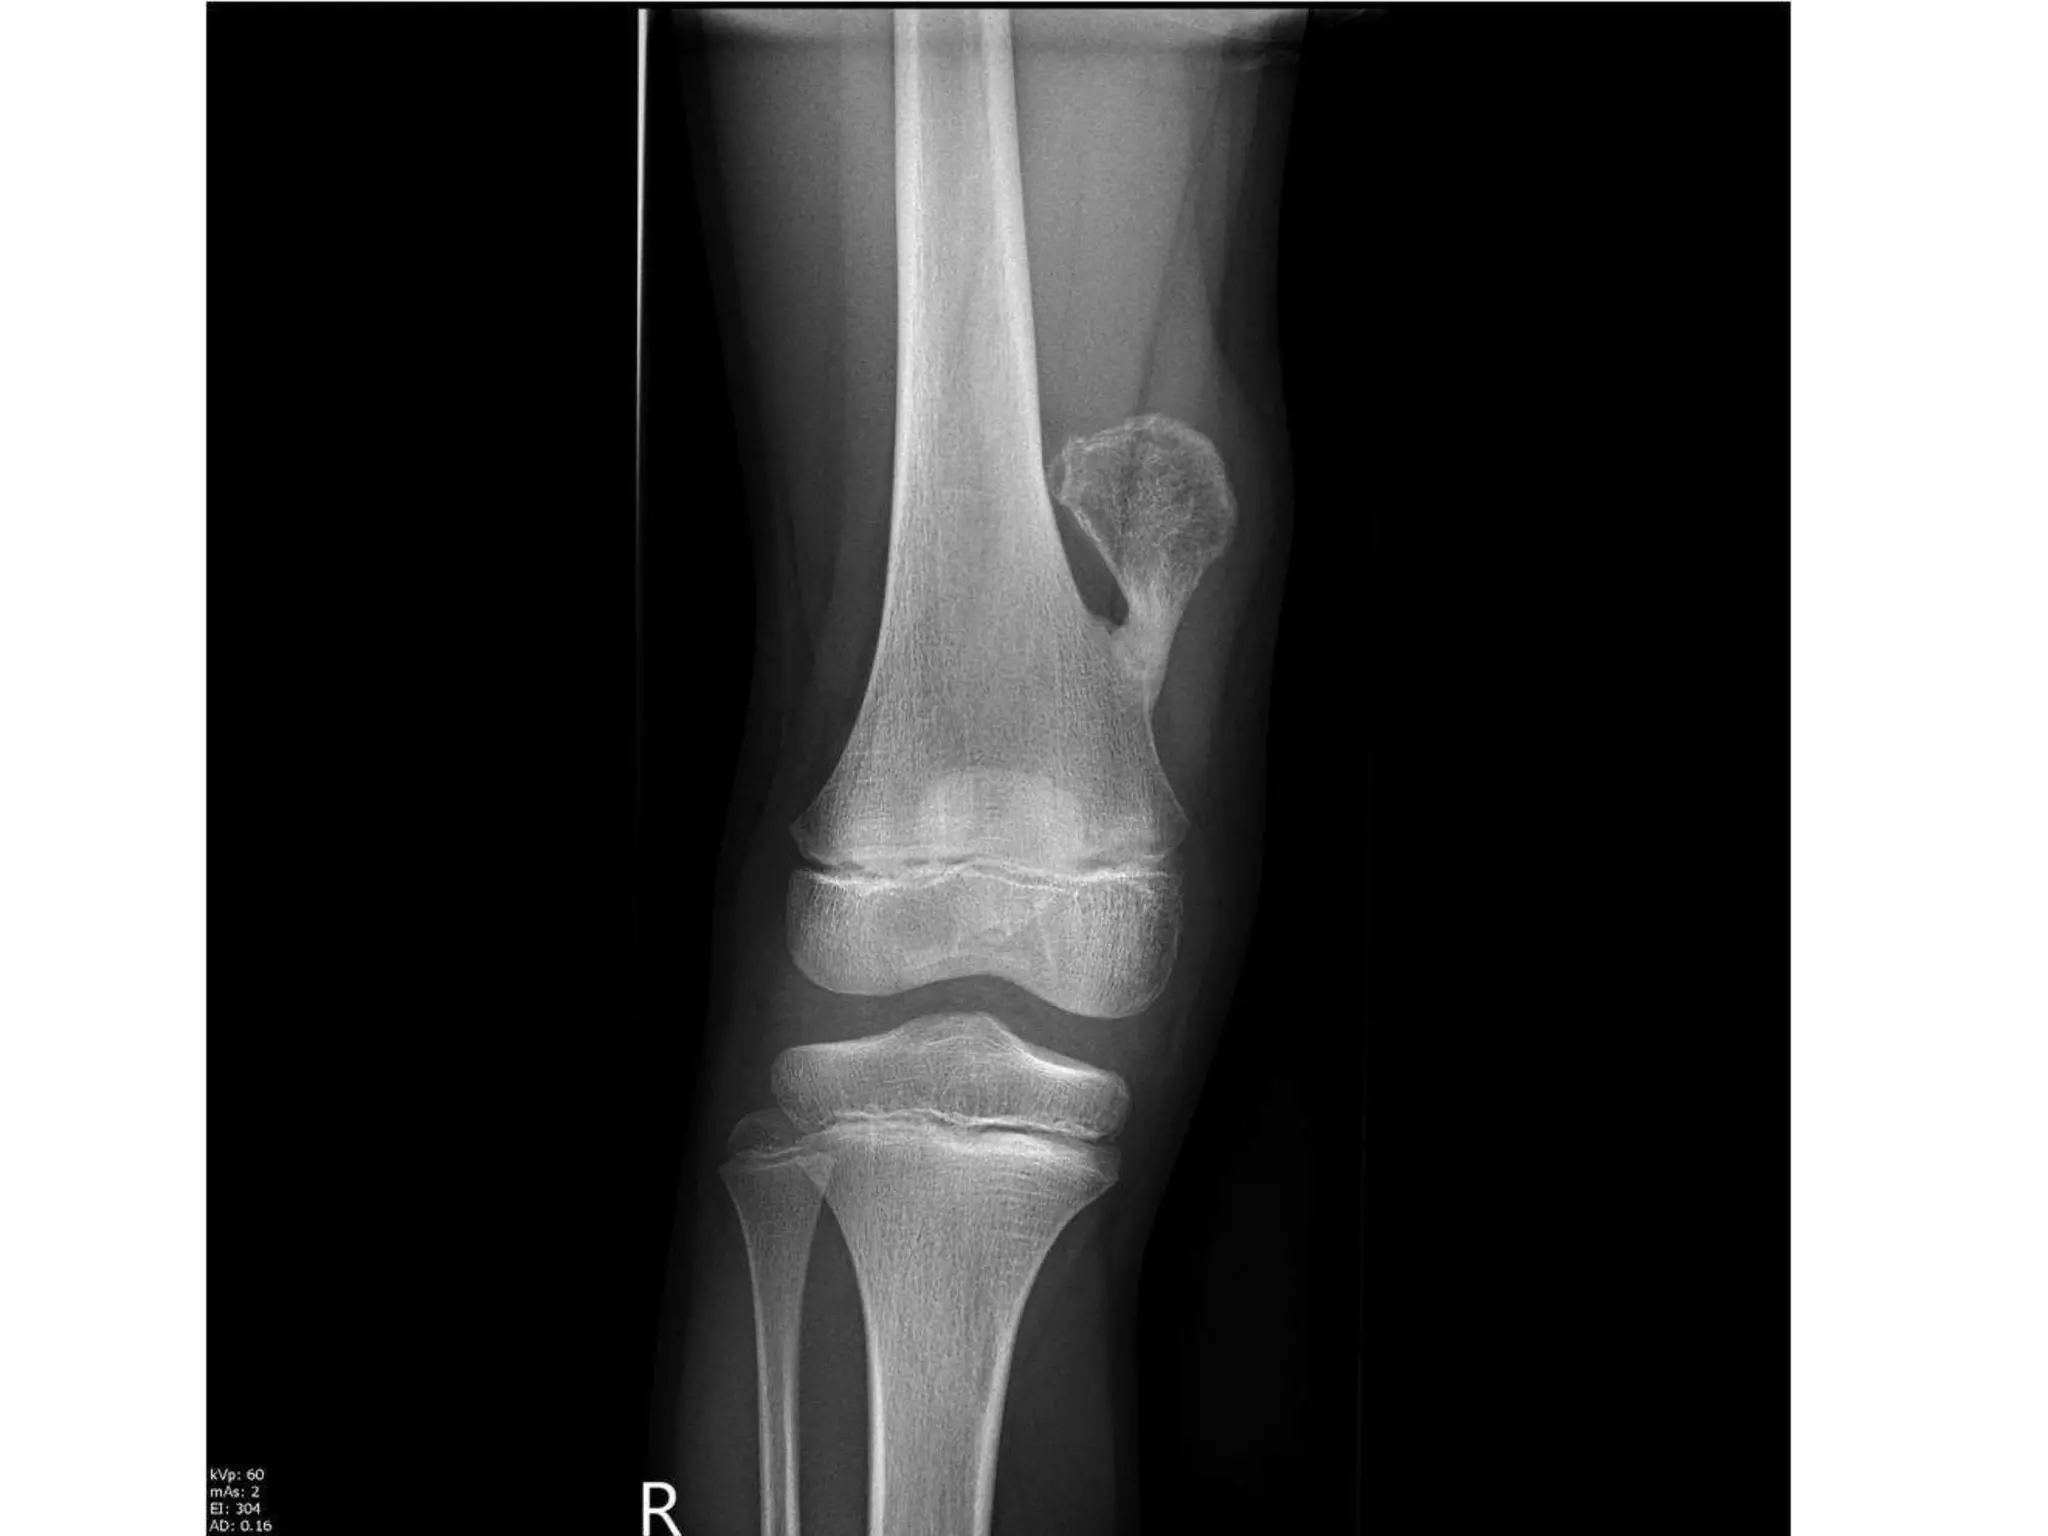

OSTEOCHONDROMA

• The lesion appears as a bony protuberance with well-defined limits,

• The pathognomonic feature is that the host bone flares from the

• Some are pedunculated with a cauliflower-like summit; others have

• Pedunculated osteochondromas typically point away from the joint,

• MRI demonstrates the classic cartilaginous cap which

The cap is typically thicker in children and diminishes

• Osteochondromas tend to grow with skeletal

• The risk of malignant transformation is rare, possibly

• In asymptomatic lesions, treatment is not indicated.

where local pressure effects may occur or in adults

removal.